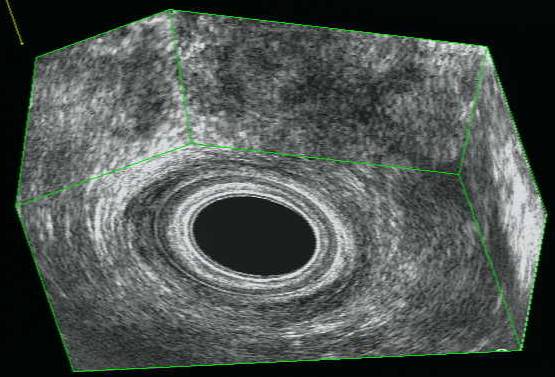

CANALE ANALE NORMALE: RICOSTRUZIONE 3D

Sfintere anale interno |

Fionda del

puborettale

Sfintere anale esterno

Muscolo longitudinale |

Nelle donne l'ecografia

tridimensionale ha documentato in modo molto preciso uno

sfintere esterno

più corto anteriormente rispetto

alla sua porzione posteriore

|

Sfintere anale interno

Sfintere anale esterno |